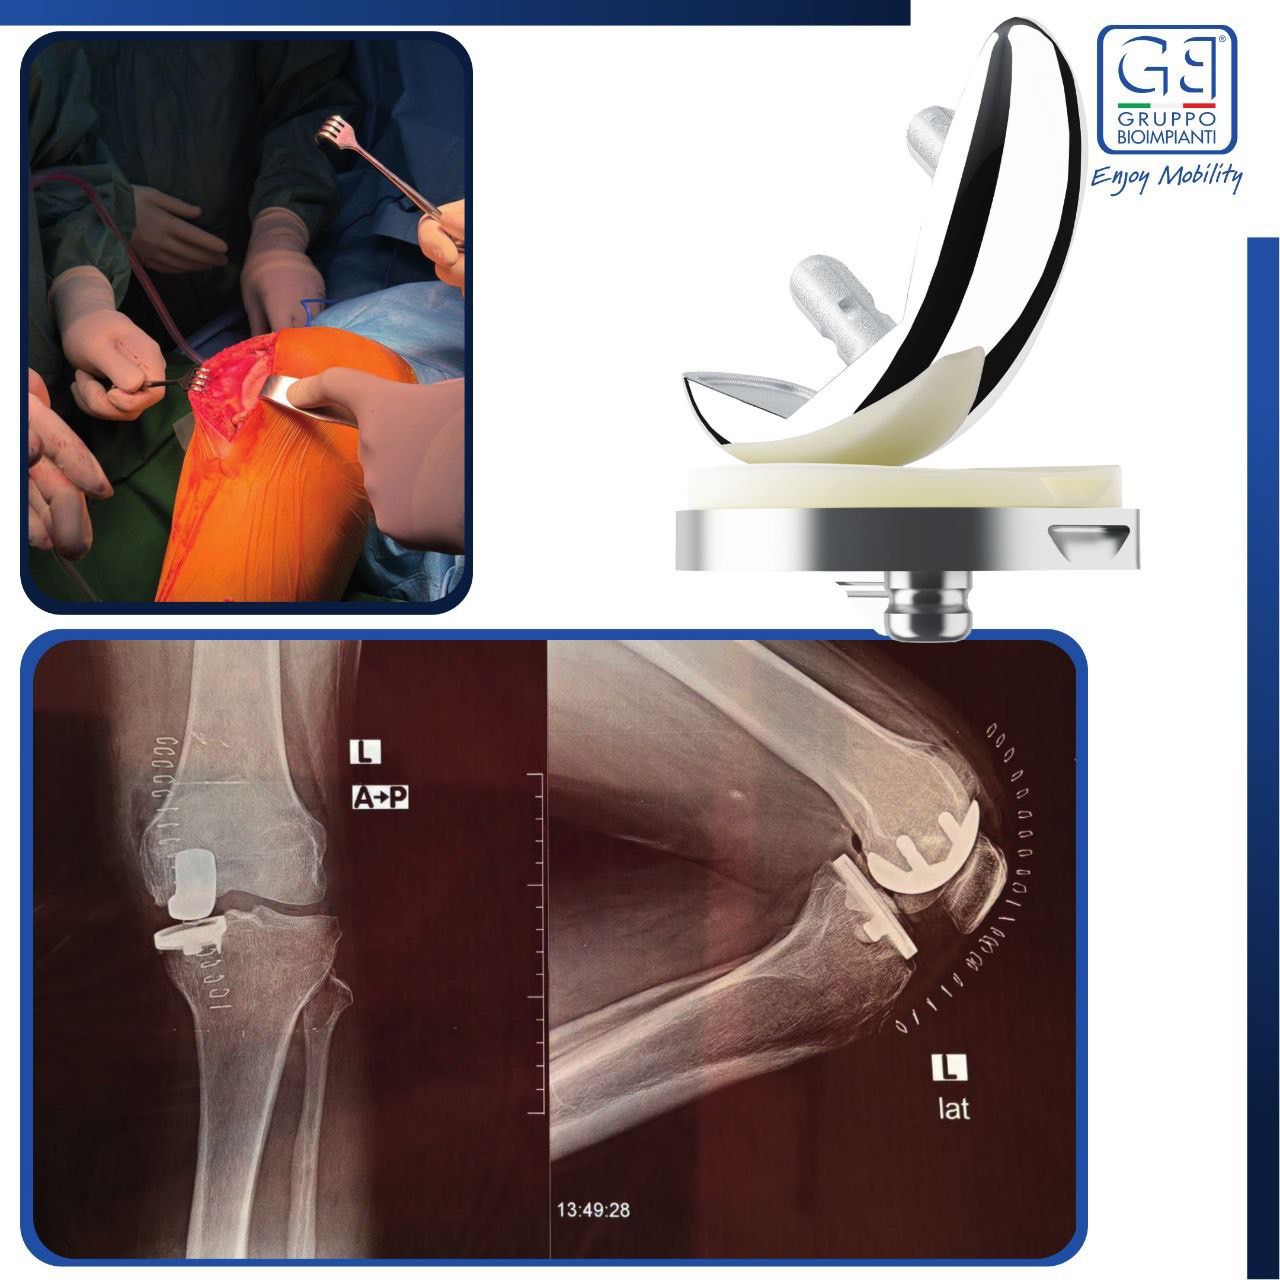

جراحة مفصل الركبة الجزئي

مواكبة لكل ما هو حديث ومتطور في مجال الصحة ولأول مرة في ليبيا تم إجراء ثلاث عمليات ” جراحة مفصل الركبة الجزئي ” بنجاح على هامش الدورة التدريبية الخامسة لجراحة الركبة والتي أقيمت في مدينة صبراتة تحت إشراف مجلس التخصصات الطبية والجمعية الليبية لجراحة وتنظير المفاصل في مستشفى الرشيد .. حيث تهدف هذه الجراحة إلى استبدال الجزء التالف فقط من مفصل الركبة مع الحفاظ على الأجزاء السليمة وتستخدم لعلاج خشونة الركبة المحدودة في جزء واحد ..

كما نشكر شركة النداوة لإستيراد الأدوية والمعدات الطبية و الوكيل الحصري للمفاصل الصناعية نوع gruppo وهذا ما نشرته شركة #gruppo_bioimpianti في صفحتها الرسمية عن هذا الحدث المميز